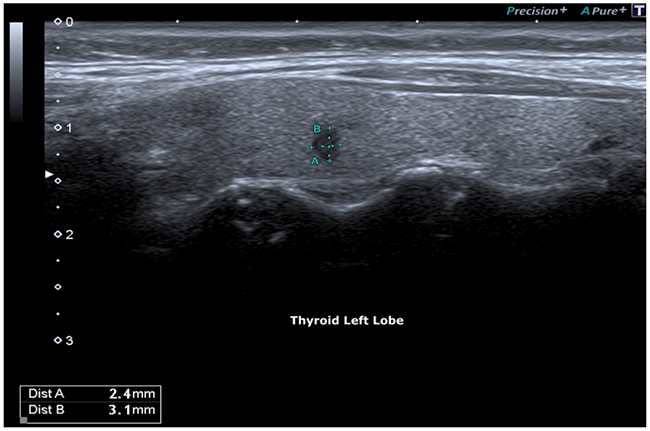

Bidimensional ultrasonography (DUS 2) using high frequency probes (13 - 15 MHz) (Toshiba Aplio 500) highlighted a highly suspicious micro-focus of the left lobe, of radial shape with markedly hypoechoic echostructure, irregular margins, size 0.3 cm (classified TI-RADS 5, very high risk lesion ATA guidelines).

Figure 1: Hypoecogenic micro-focus, irregular margins.

Figure 2: Micro-focus, irregular margins: 3 mm.

The micro-focus identified was localized at the middle third of the left lobe, presenting a radial shape, markedly hypoechoic echostructure, irregular margins, size 0.3 cm, characteristics with a high predictive for malignancy value (p <0.001) [19].